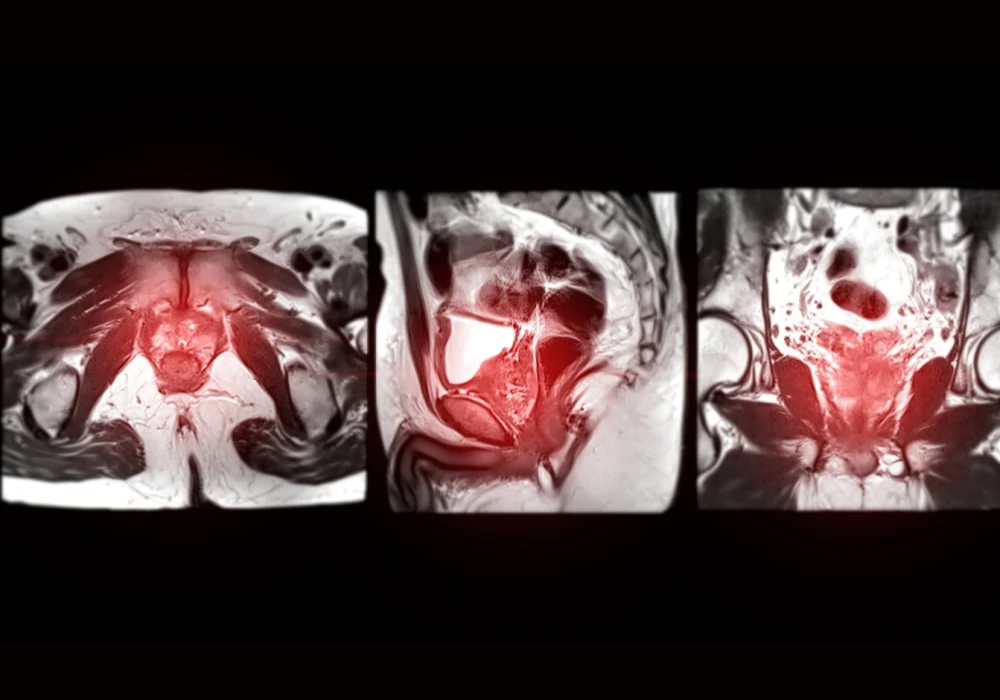

Radiology reading rooms are intentionally dim to optimise image contrast and reduce glare, supporting accurate interpretation. However, prolonged time in such settings coincides with reduce